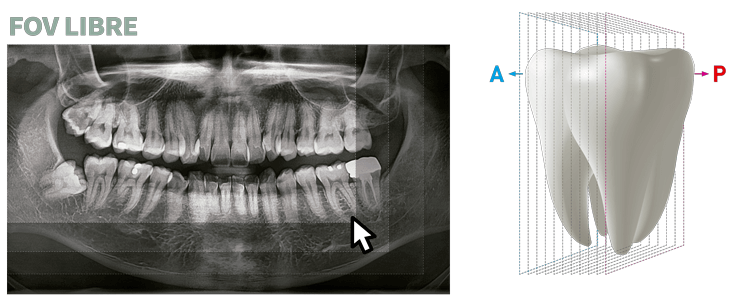

FUNCIÓN INSIGHT DE SEGUNDA GENERACIÓN

Insight PAN es capaz de tomar una multicapa de la imagen panorámica proporcionando un aspecto de profundidad a través de un punto focal único. Insight 2.0 tiene la función de FOV gratuita mejorada para capturar sólo el área de interés.